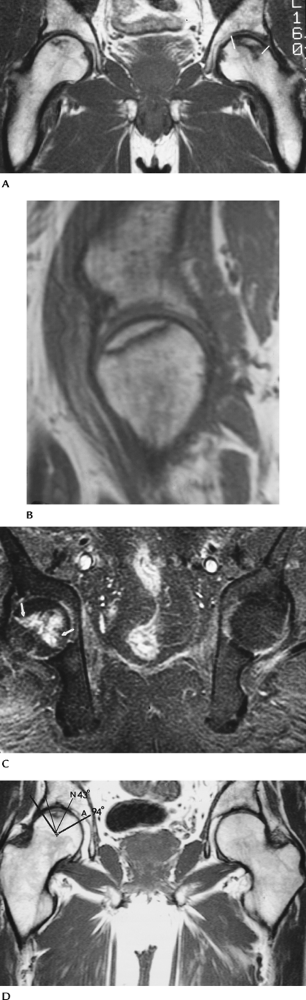

FIGURE 4-33 MRI of AVN. (A) Coronal T1-weighted image of bilateral AVN with greater articular involvement on the left (lines). (B) Sagittal T1-weighted image demonstrating articular surface involvement. (C) Fat-suppressed T1-weighted postcontrast image shows enhancement at the margin of the necrotic bone (arrows) caused by revascularization. (D) Coronal T1-weighted image demonstrating a simple method to calculate the weight-bearing surface involvement. Angle A (thick black lines)

is formed by lines from the center of the femoral head to the weight-bearing margins. Angle N is formed by lines from the necrotic margins to the center of the femoral head. N/A × 100% = % of weight-bearing involvement. In this case 43/94 = 46% indicating a poorer prognosis. |